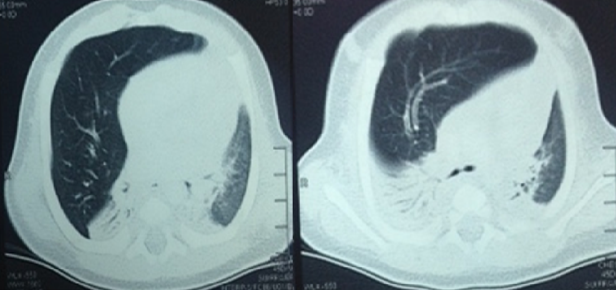

Figure 2. CT scan of the chest showing right middle lobe emphysema, collapse of the right lower and upper lobes, and mediastinal shift to the left side.

Urgent thoracic evaluation was acquired. The thoracic surgery team determined the presence of lung vascular markings in the right side, raising suspicion of congenital lobar emphysema. The patient rapidly progressed to respiratory distress requiring initiation of mechanical ventilation, hence an urgent computed tomography (CT) scan of the chest was performed. This confirmed the diagnosis of congenital lobar emphysema of the right middle lobe and mediastinal shift to the left (Figure 2).